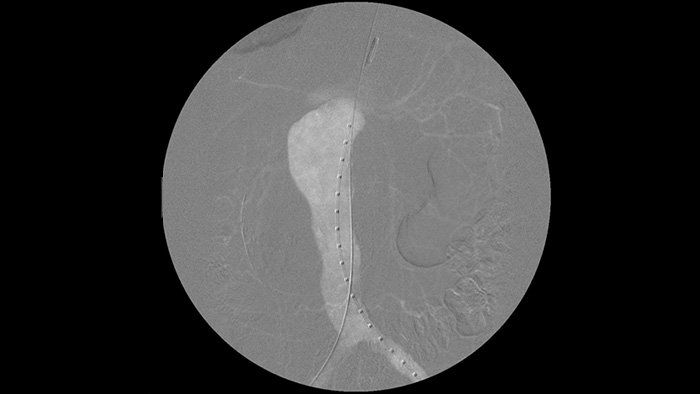

It’s easier to see a guide wire compared to our old system. Now you can see the tip and the angle of the wire that’s going around, even with 0.014 inch wires.

That’s because Zenition compensates for what’s metal and what’s moving."

Dr. R. Vila, MD

Bellvitge University Hospital, Barcelona, Spain